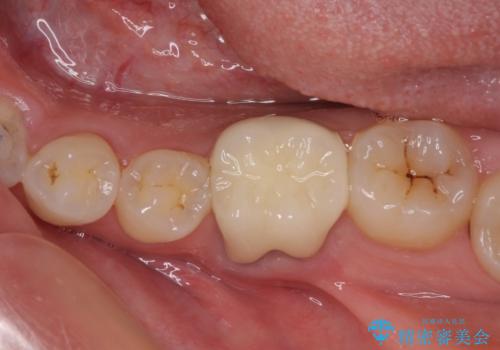

奥の銀歯も気になっていたため、矯正治療後にセラミッククラウンにて補綴することとしました。